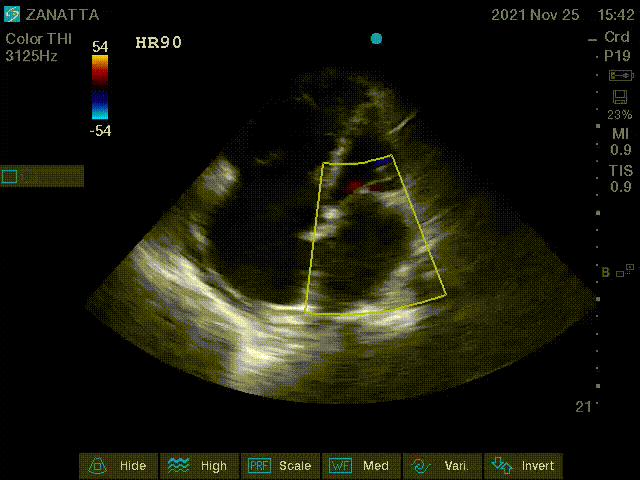

Onto colour doppler imaging.

Apical Four Chamber with Colour